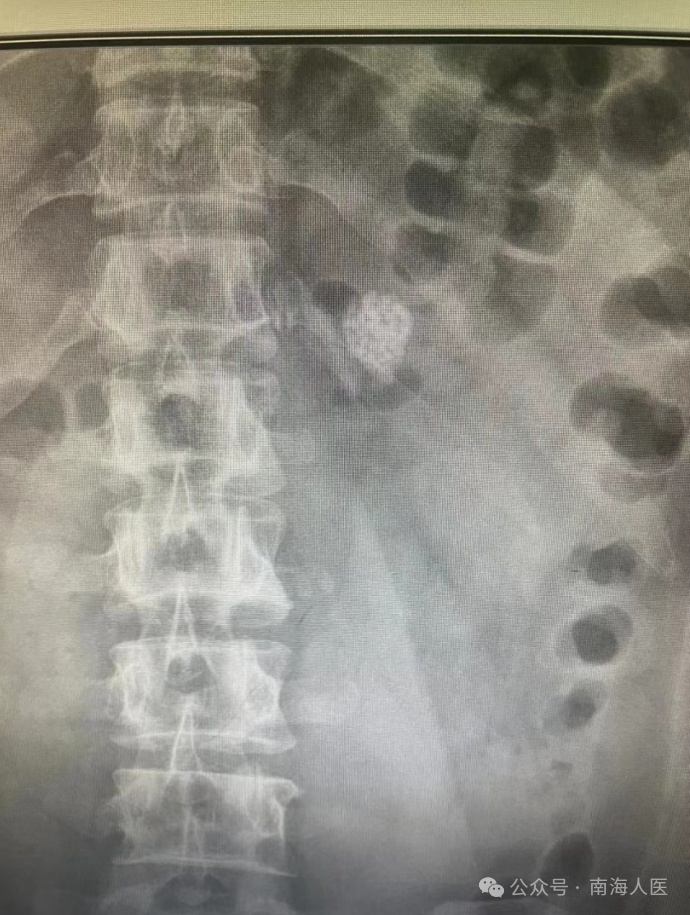

近日,32岁的韦先生因反复左腰部疼痛,来到南海区人民医院泌尿外科二区就诊。

检查显示,韦先生的结石位于肾盏憩室,结石体积大、位置隐蔽,且靠近腹壁。如果采用经皮肾镜碎石术出血风险太大,采用输尿管软镜碎石术难以找到结石位置或者难以取干净。

为了控制出血风险和尽量取干净,在多科室的配合下,泌尿外科二区主任冯权尧尝试用腹腔镜做肾实质切开取石。手术过程中最大限度减小创口,术中基本无出血,结石也完全取净,成功完成了首例腹腔镜下肾实质切开取石术。